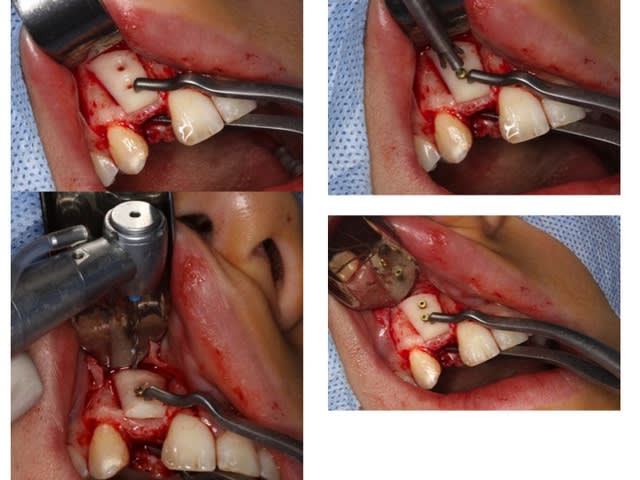

Greffe 2D:

Greffon mince en vestibulaire qui coulisse sur les deux vis, on écarte du SR ( photo avec syndesmotome faucille) on glisse dessous les fragments copeaux d'os et on ressert un peu à la fin

Donc le greffon cortical sert de membrane pour protéger le lit de copeaux

Nettoyage du SR avec fraise boule pour retirer tout les tissus fibreux sur l'os et accessoirement ouvrir les espaces médullaire ( en théorie ) Ici grosse frayeur car l'apex de 11 est dans le vide ainsi que la moitié de la dent: toute la face vestibulaire et distal... Merci Mrs les ortho.....

Préparation des trous de vis en diam 1,5 pour vis de 1,3 et cuvette pour les têtes de vis

Pince de barth pour maintenir le greffon et forage dans les trous au forêt de 1mm et mise en place des vis. Le greffon est libre, pour pouvoir régler l'épaisseur souhaitée.

Le greffon est soulevé pour glisser dessous le broyât osseux

Serrage final des vis et élimination des angles tranchants à la fraise boule diamantée